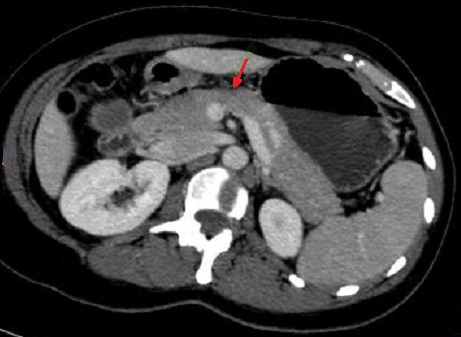

Image d'une pancreatite aigue

avec des foyers de absence de rehaussement a

hypodense apres de injection contrast intraveineuse

( fleche rouge ) . Image radiologique TDM phase

arteriel |

Aspect de reactionnel des

ganglions peri- pancreatique ( fleche rouge ) |